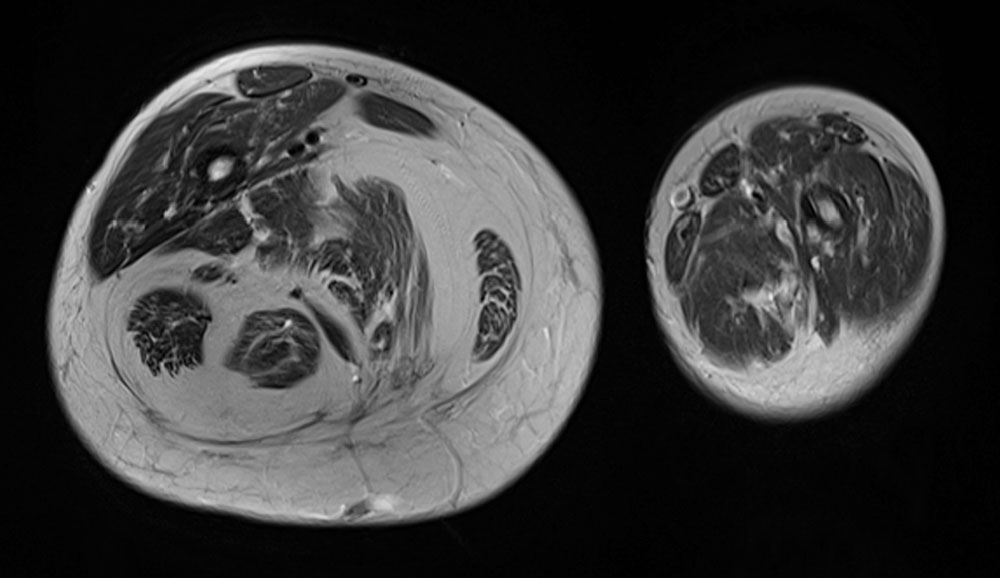

Automatic pneumatic compression devices dynamically exert external compressive pressure on the affected limb via pressure chambers inflatable by machine. This practically massages out the edema by the repeated application of external pressure. These devices only make sense if mobilizable edema fluid is also present (lymphedema or phlebedema). Soft tissue hyperplasia, which can also look clinically like lymphedema, cannot be treated with a compression device. If necessary, this must be verified more precisely by imaging.